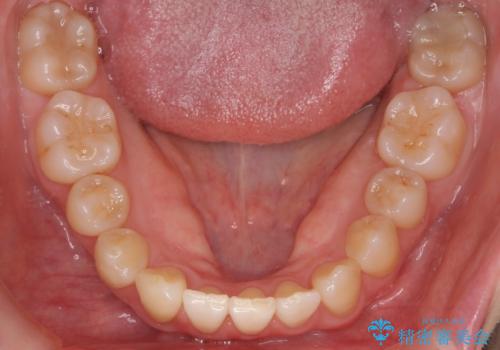

- 前歯のがたつきを主訴に来院。

下の前歯は生まれつき1本少ない状態でした。

左上の犬歯が入りきらずねじれており、かみ合わせもずれていました。

左上の小臼歯を1本抜いて治療しています。

前歯は内側に傾いており(ラビッティング)、過蓋咬合(深いかみ合わせ)を呈していました。

難しい治療でしたが綺麗に咬み合わせることができ、また前歯もしっかり当たるように治療できました。